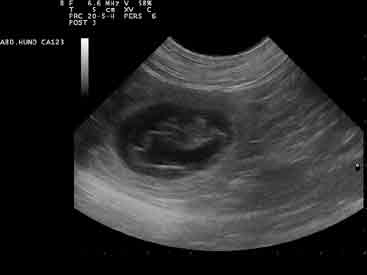

Leider passierte tatsächlich nichts, so dass wir Lina und die Welpen in das Auto setzten und nach Dortmund zur Tierärztin fuhren. Als wir aus dem Auto stiegen, stellten wir fest, dass Lina im Auto eine sehr fest gewordene Nachgeburt von der zweiten Hündin rausgepresst hatte. Das konnte doch der Grund für  Stocken der Geburt sein. Etwas entspannter ließen wir Lina röntgen und konnten sehen, dass wie erwartet noch 2 Welpen da waren, die auch richtig lagen. Zur Sicherheit machten wir dann noch ein Dopplerultraschall,  um zu sehen, ob es den beiden noch gut ging. Alles war o.k. Frau Dr. Möhrke spritze Cacium und schickte uns wieder nach Hause.